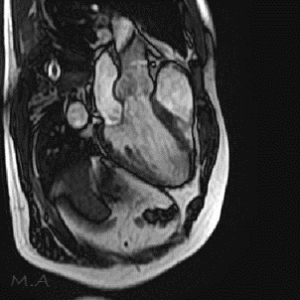

MRI

MRIとはMagnetic Resonance Imaging(磁気共鳴画像法)の略で、強力な磁石と電波を使って様々な角度から体の断面を画像化する検査です。

X線を使用しないため、放射線被ばくの心配がなく、軟部組織(筋肉、靱帯、神経など)の描出に優れており、がんの有無や広がり、転移の有無などを調べることができます。また、造影剤を用いずに血管を描出することが可能です。

当院ではCanon社製Vantage Fortian MRI 1.5Tを設置しており、主に脳血管疾患、脊椎疾患、閉塞性動脈硬化症などの下肢疾患、腹部疾患、心臓疾患、関節等の検査を行っています。